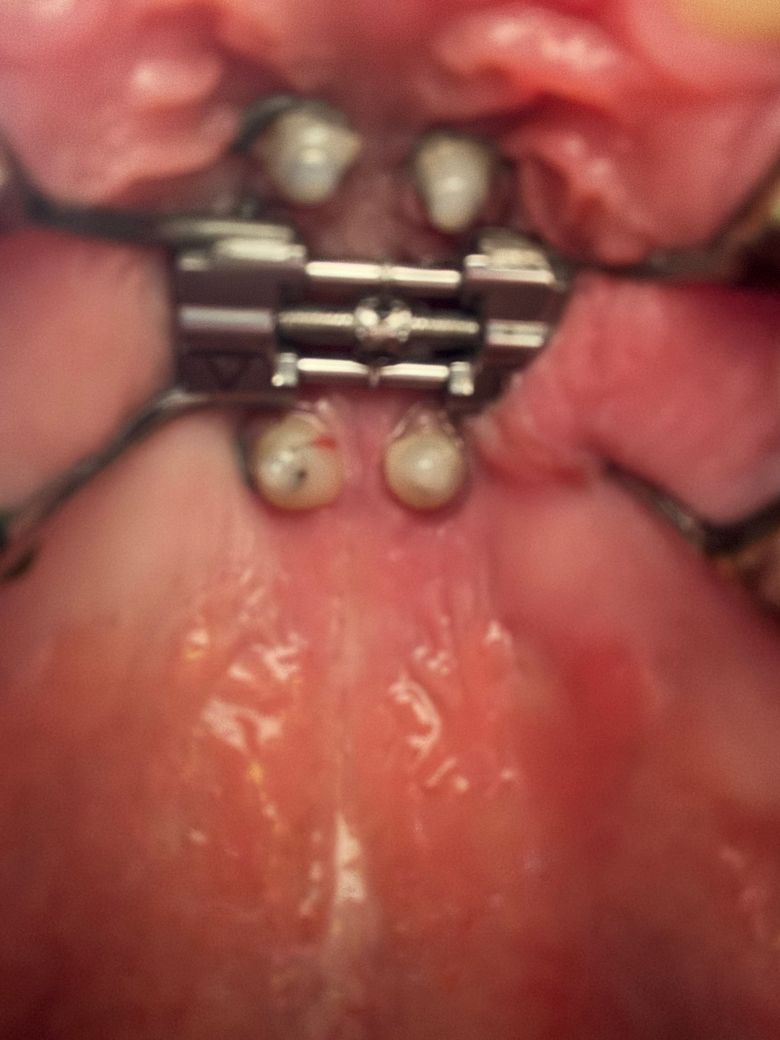

잇몸을 잘라냈는데 괜찮은 건가요??

악궁 장치 다리가 잇몸을 압박해서 염증이 났습니다.

그래서 오늘 악궁 장차 다리랑 염증 부위를 좀 잘라냈는데 사진으로 보니까 상처가 좀 많이 벌어진 것 같아서요. 괜찮을까요? 피는 멎었습니다

• 1번 째 사진

상처부위가 많이 벌어져있어 회복이 더딜 수도 있어보입니다. 해당 치과에 문의해보시는 게 좋겠습니다.